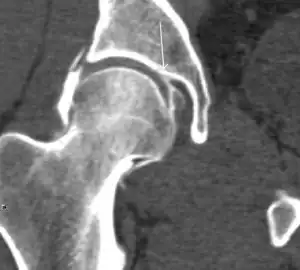

Computed Tomography

Due to radiation concerns, CT has been relegated after MRI in the study of intra-articular causes of hip pain. The only exception where CT is considered superior to MRI is in bone tumors, because of its ability in characterizing matrix calcifications, and in depicting the anatomy of acute traumatic fractures. Typical matrix calcifications include the following: (a) osteoid mineralization, like a dense cloud, (b) chondroid calcification, reproducing a punctate popcorn pattern, or (c) fibrous calcification, ground glass-like appearance. There are also tumors that typically do not show matrix calcification. CT is also used for accurate localization of the nidus in osteoid osteomas and this must be differentiated from Brodie’s abscess or a stress fracture. The current standard treatment of osteoid osteoma is percutaneous radiofrequency ablation and this is usually performed under CT guidance.[1]

Quite often, CT is widely available unlike MRI, especially in the acute setting. CT is performed in this setting when doubt about the existence of a fracture persists following plain radiograph. Modern multidetector computed tomography (MDCT) shows results comparable with MRI for detecting occult fractures.[1]

Due to the submillimeter resolution of MDCT arthrography, many authors consider this technique complementary to MR arthrography. It may even have superior sensitivity in detecting cartilage pathology, but lesser detecting labral tears.[1]

CT can also be used to obtain accurate measurement of the femoral version and torsion. The femoral version is measured by an angle formed between a line through the femoral head-neck axis and another horizontal line drawn between both ischial tuberosities. Normal values range between 5 and 25°. Retroversion is considered abnormal.[1]